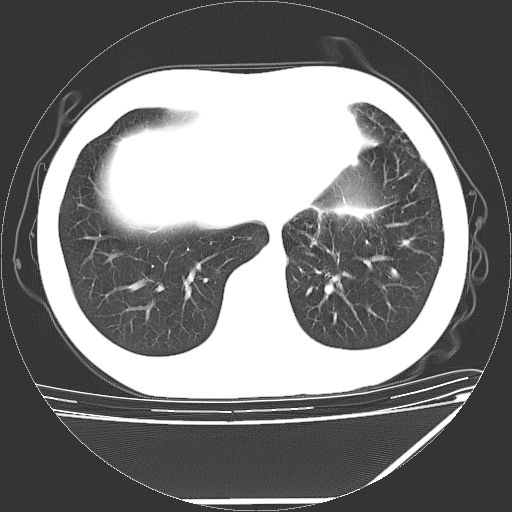

男,13岁,咳嗽、咳痰伴发热一周。

中上纵隔见多枚淋巴结肿大,部分相互融合成团片,左肺门增大,上叶支气管变窄,肺内多处斑片状 索条状及棉絮状致密影。临床“男,13岁,咳嗽、咳痰伴发热一周。”首先考虑:原发综合征!不除外淋巴瘤可能!

纵隔多发肿大淋巴结,部份有融合改变。双肺血管气管束增厚,以肺门为中心向外周散发,以左肺下叶为明显。考虑淋巴瘤可能性大。不除外原发综合征。

淋巴瘤可能性大并肺部侵犯。